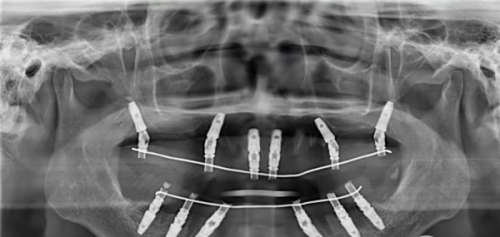

在种牙方面,患者在手术前需进行口腔全方面检查,对于重度牙周炎不能调节的牙齿进行拔除,对余留牙齿牙周进行正常牙周调节。接着制作种植牙的手术导板,根据 CT 结果以及口腔模型制作或者数字化印模制取,使手术更为精细。然后制备螺纹,用丝锥进行预备牙槽窝的骨壁上的螺纹,末尾缝合伤口,待种植体与牙槽骨紧密愈合后,安装烤瓷或全瓷的修复冠进行上部修复。整个种牙流程科学严谨。